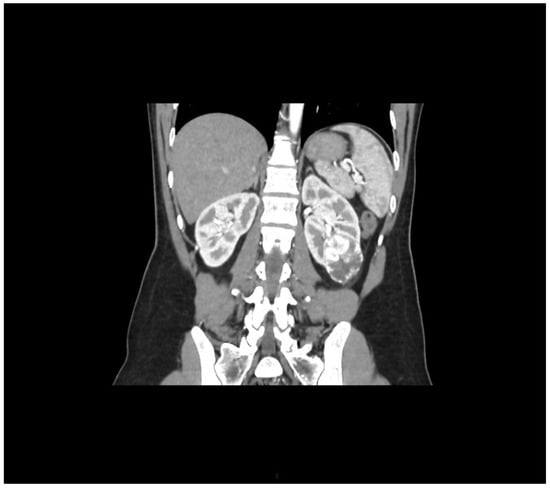

During staging for breast cancer, an incidentally detected well-vascularized mass in the lower pole of the left kidney measuring 43 × 32 mm was identified on abdominal ultrasound. MSCT urography described a relatively well-defined soft tissue mass with intratumoral necrosis, measuring 45 × 40 × 39 mm, posterolateral to Gerota’s fascia. Radiologically, the findings were suggestive of renal cell carcinoma (RCC), although oncocytoma could not be excluded (Figure 2).

Figure 2. Arterial-phase multislice CT in the coronal plane shows a well-vascularized tumor at the lower pole of the left kidney.